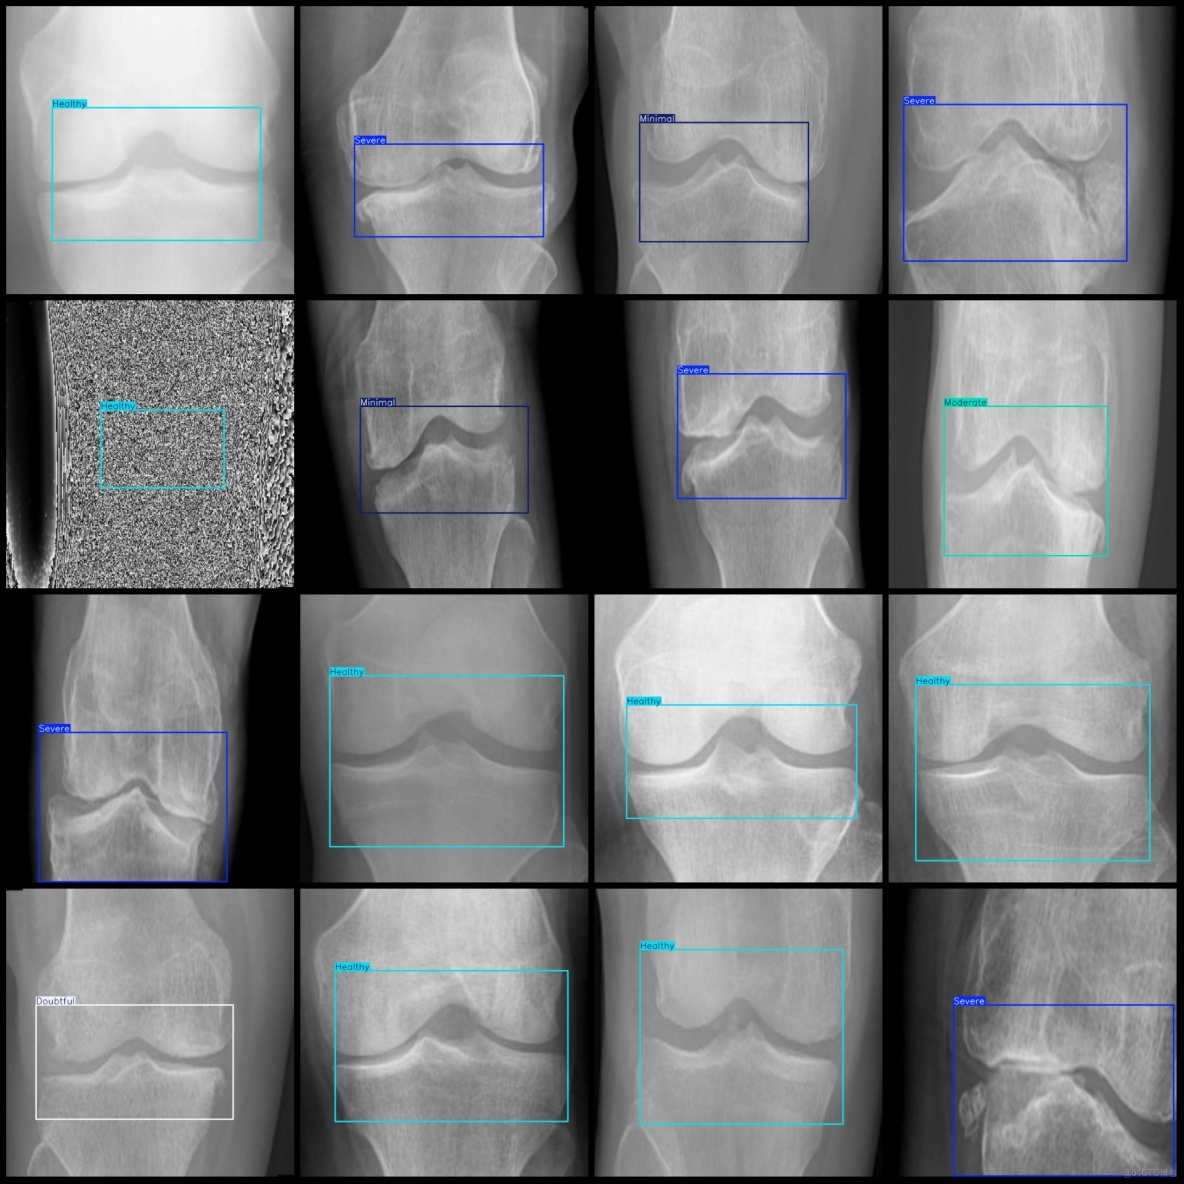

圖片預覽:

智慧醫療膝蓋骨關節炎嚴重程度檢測數據集VOC+YOLO格式8000張5類別_xml文件

智慧醫療膝蓋骨關節炎嚴重程度檢測數據集VOC+YOLO格式8000張5類別_數據集_02

標註類別名稱(注意yolo格式類別順序不和這個對應,而以labels文件夾classes.txt為準):["Doubtful","Healthy","Minimal","Moderate","Severe"]

每個類別標註的框數:

Doubtful (待定) 框數 = 1414

Healthy (健康) 框數 = 3700

Minimal (極輕度) 框數 = 819

Moderate (中度) 框數 = 730

Severe (重度) 框數 = 1337